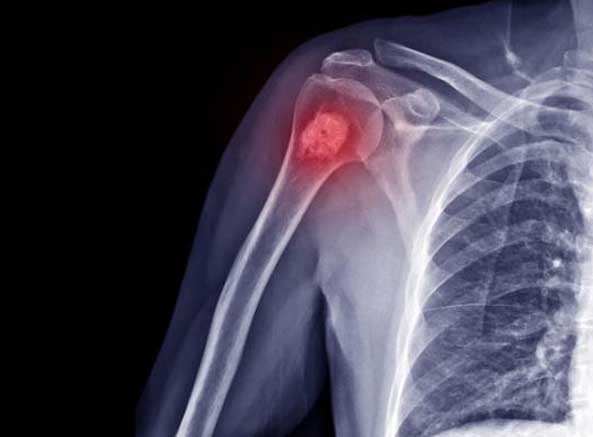

استئوسارکوم بیشتر در افراد کم سن و سال ایجاد می شود و به سرعت به قسمت های دیگر بدن نفوذ می کند. محل تشکیل این تومور نیز در بالا و پایین زانوها و شانه ها به خصوص در استخوان های بلند این نواحی است. قابل ذکر است که این تومور در صفحات رشد استخوان های ناحیه های ذکر شده ایجاد می شود.